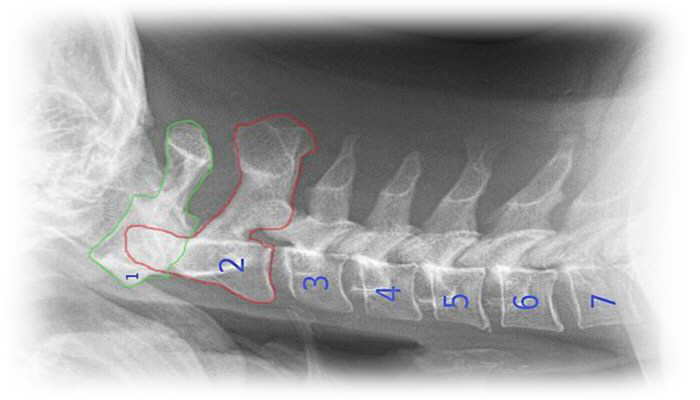

التهاب المفاصل الانتكاسى بالرقبة

DEGENERATIVE ARTHRITIS OF THE NECK